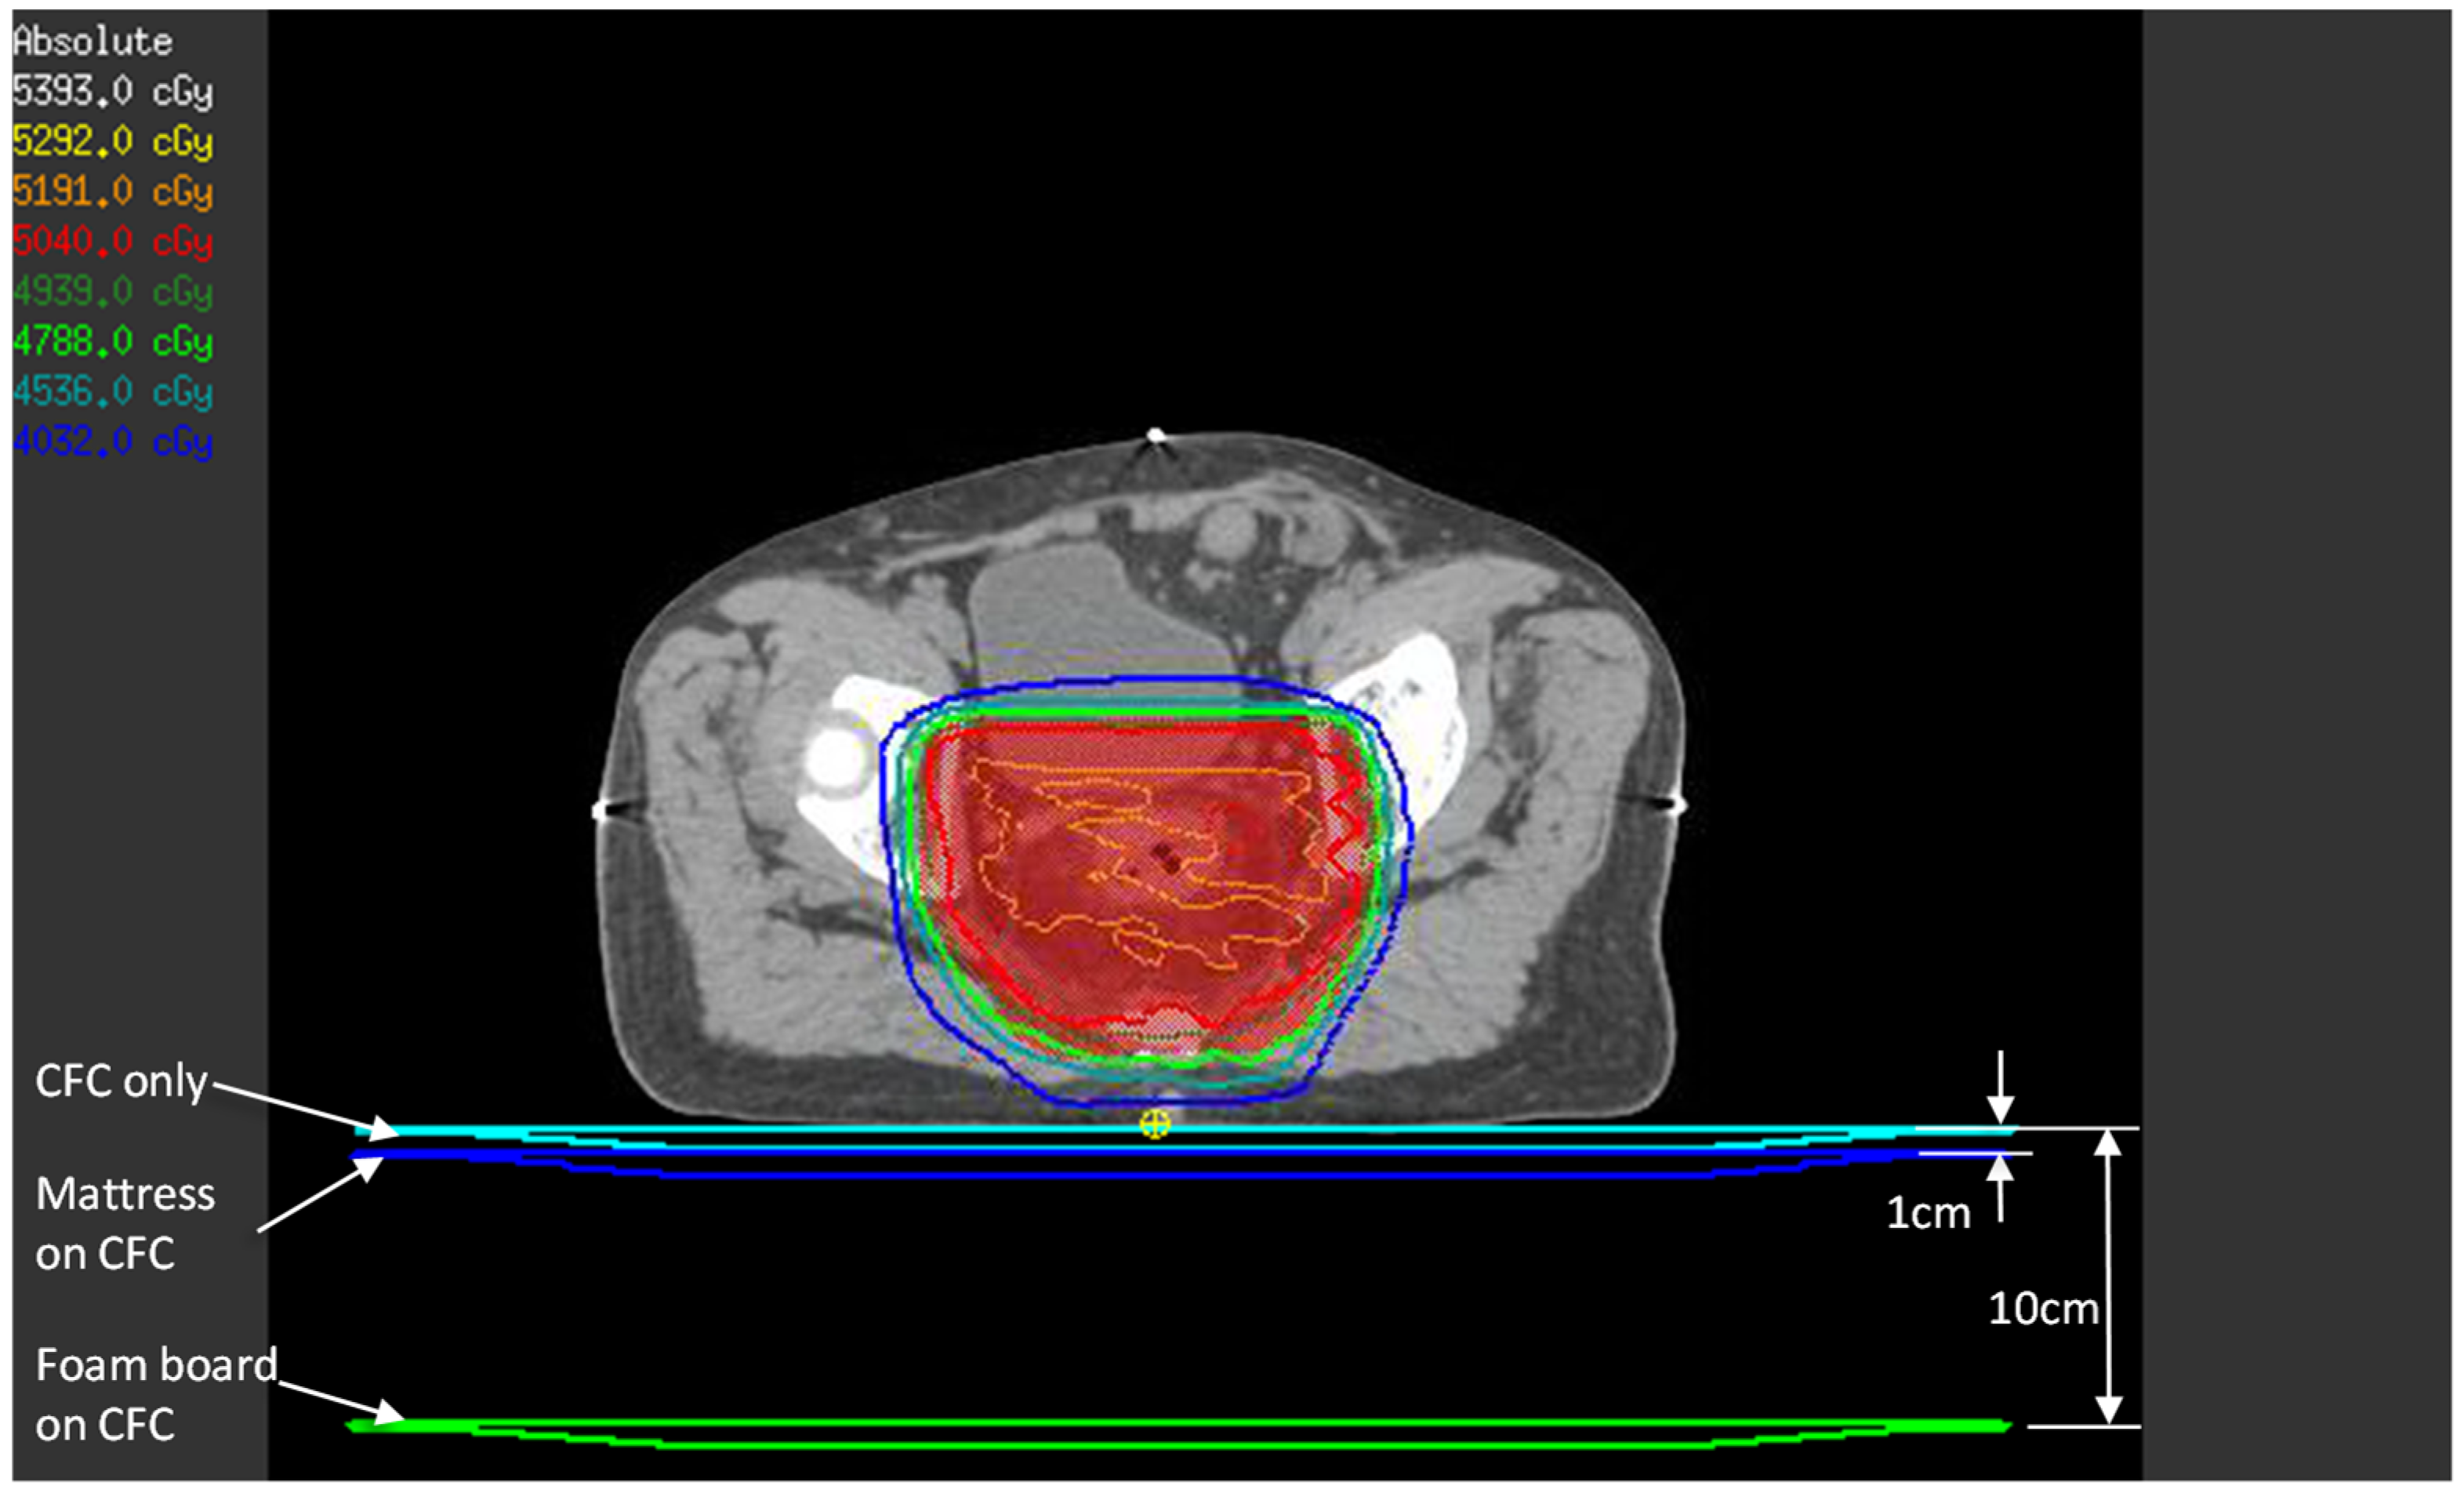

Although TPS estimation of the surface and buildup doses has accuracy issues when using a collapsed cone convolution algorithm [18], we thought it would be instructive to compare TPS calculations and the OSLD phantom measurements. The patients’ treatment CT images and VMAT plans were used in this estimation. To simulate the effect of each setup, the 1 cm water-equivalent couch model that we use clinically was placed directly under the patient (simulates CFC only setup), 1 cm from the posterior of the patient (simulates mattress setup), and 10 cm from the patient’s posterior surface (simulates foam board setup), as in Figure 3. A dose point was created at 1.2 mm depth from the patient’s posterior surface immediately below the beam isocenter—this represents the approximate location of the OSLD sensitive volume in the phantom experiment.

Figure 3.

TPS estimate of posterior skin dose with the three setups. For each setup (CFC only, mattress, and foam board), the three couch models shown were density-overridden to 1 g/cm3 one at a time, and beams were calculated to obtain the posterior skin dose, represented by the small yellow point of interest.